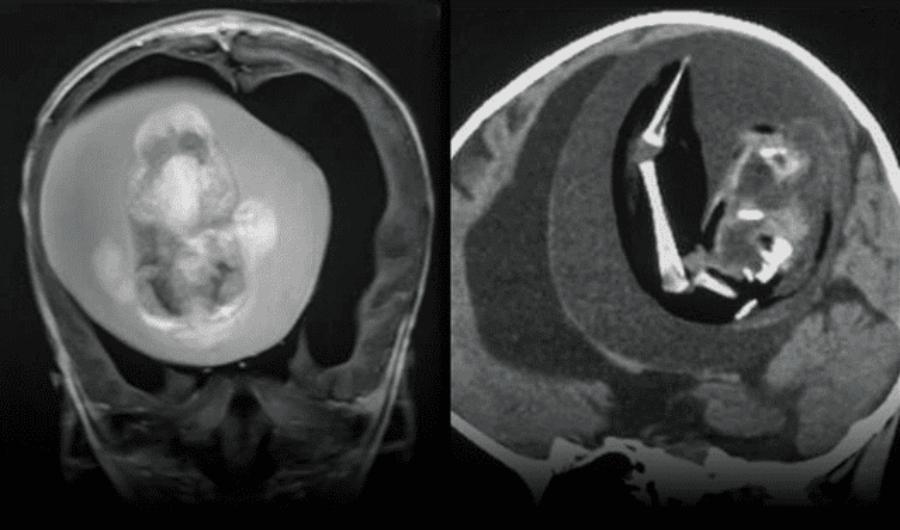

A una niña de 1 año se le practicó a una intervención quirurgica para extraer el feto de su hermano gemelo, anomalía conocida como fetus in fetu (feto en feto) o «gemelo parásito”, según informó la Universidad de Fundan en Shangái, China.

«Se identificó un fetus-in-fetu intraventricular, un gemelo diamniótico monocoriónico malformado, en una niña de 1 año con retraso motor y perímetro cefálico agrandado», señala el reporte.

El fenómeno ocurre aproximadamente a 1 de cada 500.000 nacidos. Usualmente, el feto malformado aparece en el abdomen. Sin embargo, en este caso apareció en la cabeza de la menor.

Cuando eran fetos, ambos habían compartido la misma placenta, aunque separados por sacos amnióticos. Todo parece indicar que uno de ellos se mimetizó durante la gestación. Luego se alojó en el cerebro de la niña durante el proceso de desarrollo, denominado plegamiento de la placa negral.

El descubrimiento se dio luego de que la niña de 1 año diera señales de retrado en el desarrollo de sus habilidades motoras, agrandamiento en la circunferancia del craneo y acumulación de líquido en el cerebro.

Los escáneres cerebrales revelaron que el feto en la cabeza de la niña de 1 año tenía columna vertebral y dos huesos de la pierna. Además, tenía espina bífida, afección donde parte de la médula espinal queda expuesta. Cuando finalmente se extrajo, se determinó que tenía brotes de extremidades superiores y dedos.